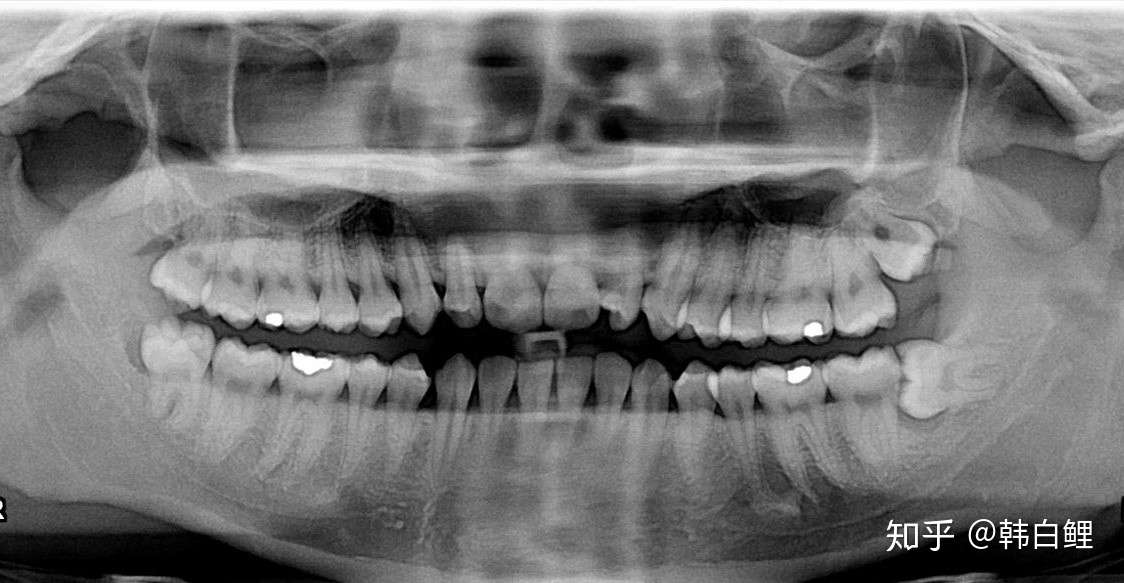

3.智齿缺失

智齿是口腔牙槽骨上的第三颗磨牙,一般有上下左右对称的4颗。

有些人觉得自己没有智齿呀?实际上它是被牙龈包裹着,像下图这样。

被牙龈包裹的智齿

在人类的进化的道路,我们的大脑挤满了头骨,下颚缩小,没有留给第三磨牙(智齿)的空间了。

并且在几千年前人类开始烹饪食物并发展农业之后,饮食变得更加柔软,不需要再咀嚼坚硬的食物。

智齿的存在显得有点多余。

对于现代人来说,智齿还是个很麻烦的东西:

一是智齿萌发的时候容易引起发热,脑壳子疼;

二是智齿长得歪歪斜斜,顶歪隔壁的牙齿,或是嵌塞食物残渣;

三是如果只有单个萌出的智齿,对颌没有相对应的牙,容易反复咬伤对颌,形成创伤性溃疡。

如果不长智齿该多好!

一项研究中智齿缺失的人口比例

大约几千年前,一种涉及PAX9基因的突变出现,导致患者第三磨牙(智齿)发育不全,智齿缺失。根据一项研究表明,韩国人的患病率达到了41%,也就是说10个韩国人里面,有4个是没有智齿的!